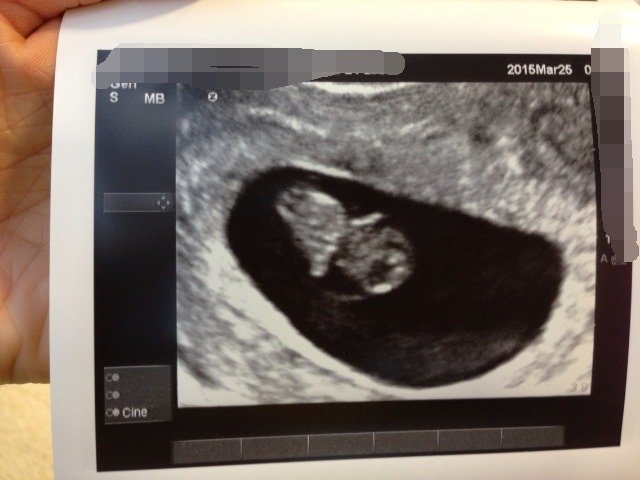

宝宝八周时的B超图,第一次看到自己的宝宝,母爱顿时泛滥吖,才真正有了怀孕的幸福感三周从一个小洞长 宝宝八周时的B超图,第一次看到自己的宝宝,母爱顿时泛滥吖,才真正有了怀孕的幸福感。三周从一个小洞长到了这么大,怪不得我体重每增加一点。。是不是初期长太快也不好? 点击展开 小QJ的麻麻。 2015-04-04 20:46 为您推荐: 其他回答 我是两个月去的,都正常。 安好可以有多好ヾ 2015-04-05 18:33 宝妈好孕o 我以为我努力na 2015-04-05 07:35 祝寶媽好孕 | 我喺超人 、 2015-04-04 23:33 祝宝妈好孕 少靓舒晴 2015-04-04 22:44 祝你好孕。。。 朋朋宝 2015-04-04 22:01 加载更多 相关问题 怀孕10周这几天肚子有点痛做了B超结果是这样的 宝妈们谁能帮忙看下,宝宝是否健康 做b超对宝宝有影响吗?因为各种原因我已经做过三次了,他们说从怀孕到生也就做五次的,现在孕九周了都不 20天里打了3次b超、对宝宝有害吗、怀孕8周